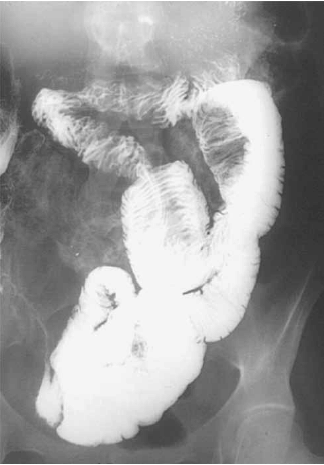

Homem de 16 anos, pardo, procurou o ProntoSocorro com queixa de dor abdominal há uma semana. Duas semanas antes da consulta, tinha apresentado quadro de dor abdominal difusa, em cólica, de grande intensidade, que cedeu ao antiespasmódico aplicado em outro serviço. Passou uma semana apresentando dores leves, esporádicas. Na semana anterior, a dor voltou e como não apresentou melhora com a mesma medicação utilizada no primeiro episódio, buscou atendimento médico. Referia dois episódios de vômitos no dia da consulta, com saída de sangue na evacuação diarreica. Negava febre, negava história de dor abdominal anterior à relacionada a esta consulta, negava comorbidades. Ao exame físico abdominal apresentava dor à palpação profunda de fossa ilíaca direita, dor à descompressão brusca abdominal, sem visceromegalias, sem massas ou tumorações palpáveis. Uma peculiaridade do exame era que, à palpação da fossa ilíaca direita, não se palpavam alças. Exames laboratoriais e radiografias abdominais não mostraram alterações. Foi internado para investigação diagnóstica e submetido a exame contrastado (demonstrado na imagem). O diagnóstico do paciente é:

(Fonte: Dr. Melvyn H. Schreiber, The University of Texas Medical Branch, Galveston, TX)